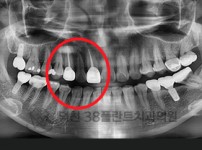

치료전후